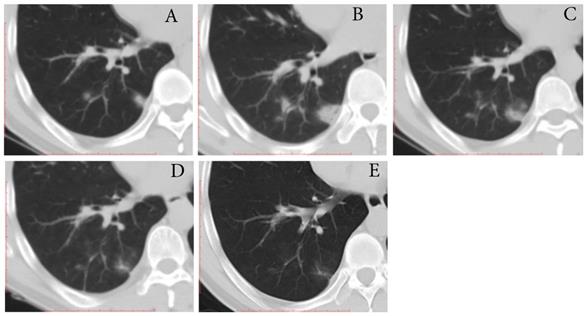

Three (16.7%) individuals showed type-PI, that is the mild increase in extent and density on the second CT scans (3 days [range, 2-4 days] after first positive SARS-CoV-2 result) and then improvement (Fig. 3). The interval time from first CT scans to last CT scans ranged from 21 to 23 days. One individual had a mild cough at the time of progress. The time for RT-PCR conversion of the three individuals ranged 19 to 21 days.

Figure 3

Typical evolution of type-PI in a 48-year-old male with asymptomatic SARS-CoV-2 infection. A, Day 0, the first chest CT showed multifocal lesions of consolidation in right lower lobe. B, Day 2, mild progression was showed on the second CT scan. C-E, Day 8-21, gradual resolution was observed on the third to last CT scans, and minimal residual GGO and linear opacities were observed on the last CT scan; And day 21 and 22, the patient had two consecutive negative results of RT-PCR. GGO, ground-glass opacity; PI, progression to improvement; RT-PCR, reverse transcriptase-polymerase chain reaction.